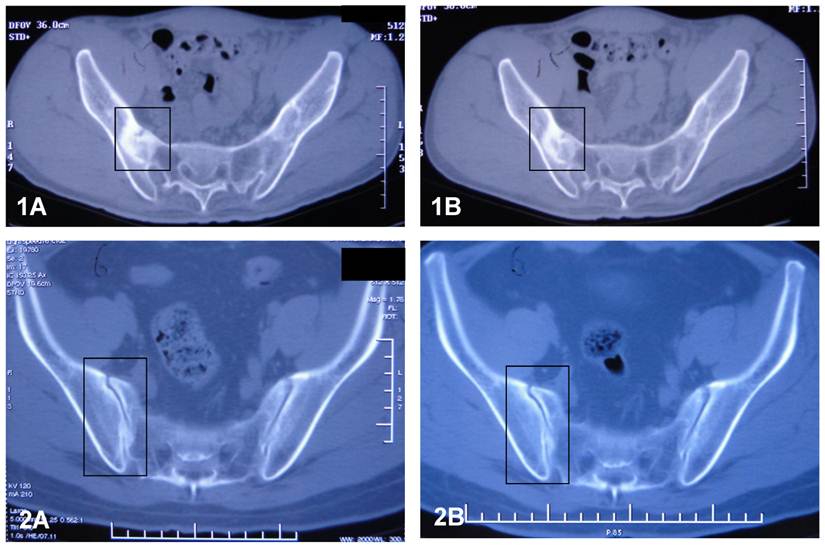

Sacroiliac joints of the patients were examined with CT after the 12 week's treatment. Compared with the observation prior to the treatment, the articular surfaces of the joints became clearer and more distinct than before. The areas of the radioactive material became decreased, indicating increased uptake of calcium deposits in the tissues. The above observation revealed that sacroiliitis, bony erosion and bone formation, hall marks of AS, got improvement during the treatment with methazolamide. Figure 4 shows the CT results.

Figure 4

CT results of sacroiliac joints of patient S (1) and patient L (2) before (A) and after (B) the treatment of methazolamide. The evidence indicates that the articular surfaces of the erosive sacroiliac joints became clearer and the area of the calcium deposits began decreased.